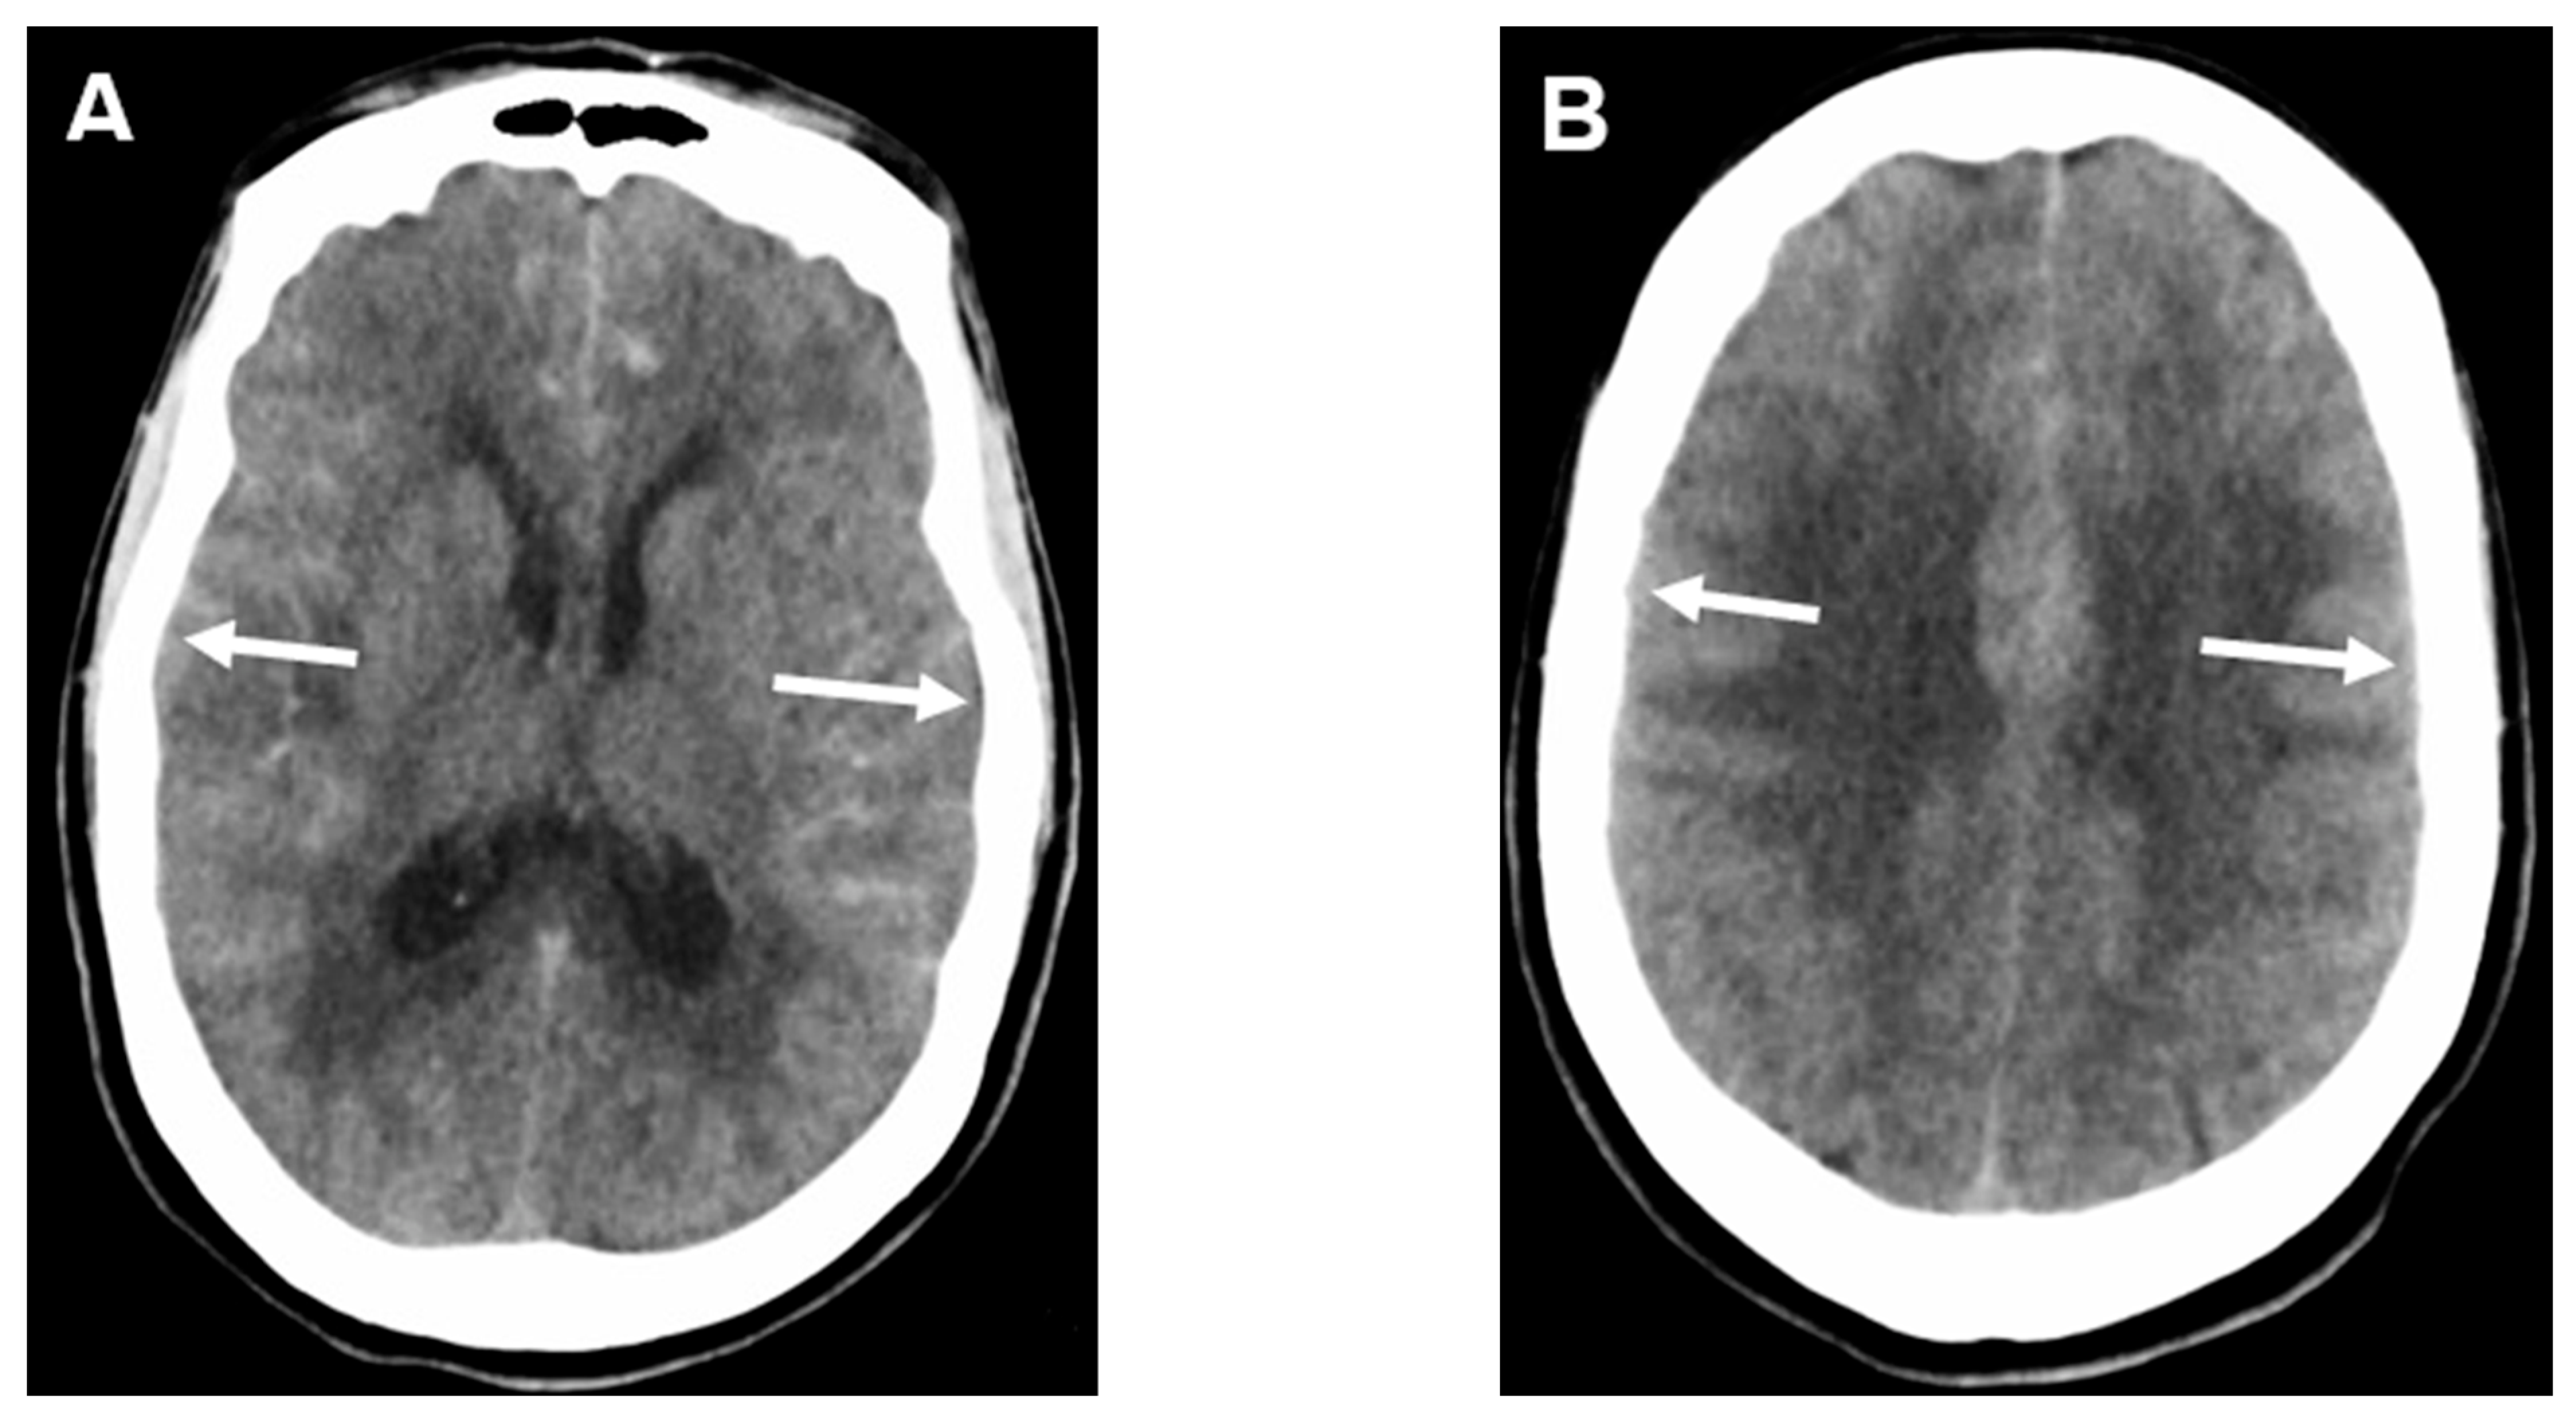

Aneurysmal subarachnoid hemorrhage (aSAH) (Figure 1) is a devastating stroke subtype with high morbidity and mortality, accounting for approximately 5% of all strokes. A systematic review of population-based studies showed that the crude incidence of aSAH in 2010 in North America was 6.9 per 100,000 person-years with an annual decline of 0.7% since 1955 [1]. However, despite significant advances in diagnosis and management of aSAH, the overall mortality remains high at 35% (range 20–67%) [2,3] and approximately 20% of survivors experience significant morbidity [4], causing a substantial economic and social burden on the patients, families, and healthcare systems [5]. Delayed cerebral ischemia (DCI) is a feared complication of aSAH, increasing the risk of morbidity and mortality, specifically in patients with a severe clinical presentation at ictus and high SAH burden [6,7]. Published data suggests DCI affects approximately 20–40% of aSAH patients and is an independent poor prognostic factor in this population [8,9,10]. DCI is classically defined as a development of a new neurological deficit(s), impaired consciousness, or infarct on imaging that commences 3 to 4 days after the initial insult and peaks around 7 to 8 days post-bleed [11]. An earlier onset of DCI prior to day 7 has been associated with higher mortality and greater infarct load [12]. Several treatment modalities targeting different pathophysiological pathways causing DCI have been studied. However, there has been minimal change in outcomes due to either DCI prevention or treatment.

Figure 1.

Subarachnoid hemorrhage. The arrows indicate both macroscopic (A) and microscopic (B) large bleeding (H&E × 10).